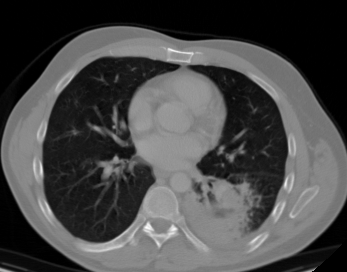

We propose a novel continual self-supervised learning (CSSL) framework for simultaneously learning diverse features from multi-window-obtained chest computed tomography (CT) images and ensuring data privacy. Achieving a robust and highly generalizable model in medical image diagnosis is challenging, mainly because of issues, such as the scarcity of large-scale, accurately annotated datasets and domain shifts inherent to dynamic healthcare environments. Specifically, in chest CT, these domain shifts often arise from differences in window settings, which are optimized for distinct clinical purposes. Previous CSSL frameworks often mitigated domain shift by reusing past data, a typically impractical approach owing to privacy constraints. Our approach addresses these challenges by effectively capturing the relationship between previously learned knowledge and new information across different training stages through continual pretraining on unlabeled images. Specifically, by incorporating a latent replay-based mechanism into CSSL, our method mitigates catastrophic forgetting due to domain shifts during continual pretraining while ensuring data privacy. Additionally, we introduce a feature distillation technique that integrates Wasserstein distance-based knowledge distillation (WKD) and batch-knowledge ensemble (BKE), enhancing the ability of the model to learn meaningful, domain-shift-robust representations. Finally, we validate our approach using chest CT images obtained across two different window settings, demonstrating superior performance compared with other approaches.